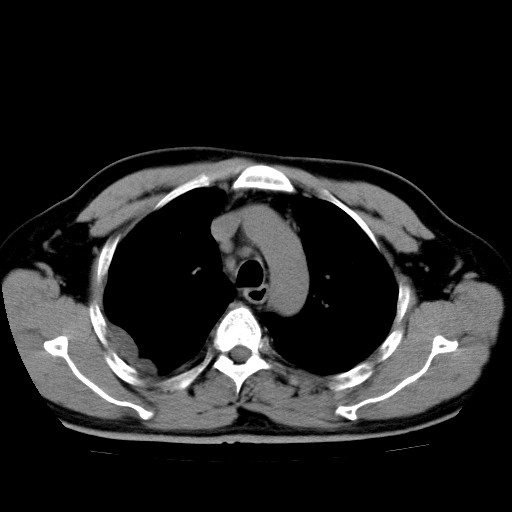

男,54岁,咳嗽,右侧胸痛10天。肺窗>150k,传不了

右肺中心型肺癌并右下肺不张,右侧胸膜纵隔转移。

右中央型肺癌并右肺下叶不张,纵隔内及右胸膜转移,右胸腔积液

考虑   右肺癌伴右下肺部分不张,阻塞性肺炎,纵隔淋巴结增大,右侧胸腔积液其他待排

考虑右肺下叶中央型肺癌并右肺下叶不张,纵隔淋巴结内及右胸膜转移。建议增强。

右下叶大片实变,肺门未见明显肿块影。有胸腔积液和纵隔内肿大淋巴结影。没有增强和肺窗,不好定。

考虑:1、右下叶周围型肺癌伴胸膜、纵隔淋巴转移?